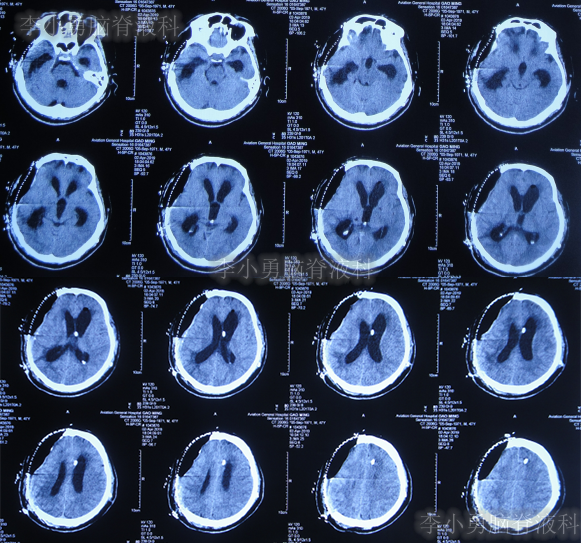

2018年8月17日(开颅术后37天),意识仍不清,查头颅CT示脑室扩张,脑膨出,有钙化(图-1);再次给予腰大池持续引流7天后拔除。

图-1:2018年8月17日头颅CT

2018年8月28日(开颅术后48天),查头颅CT示脑室进一步扩张,脑膨出加重(图-2);但意识还可以,未给予继续治疗。

图-2:2018年8月28日头颅CT